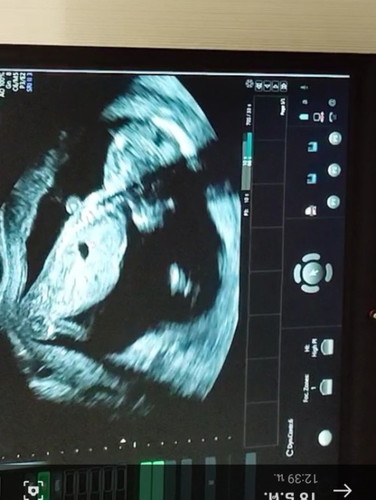

แม่ๆช่วยดูหน่อยได้ไหมคะ ว่า จู๋ น้องหรือ ขา น้องคะ

ไปอัลตราซาวด์มา คุณหมอไม่บอกอะไรเลยค่ะ บอกแค่ น้องดิ้นปกติ 😅 15 วีคค่ะ

รูปด้านข้างไม่สามารถดูเพศได้นะคะ